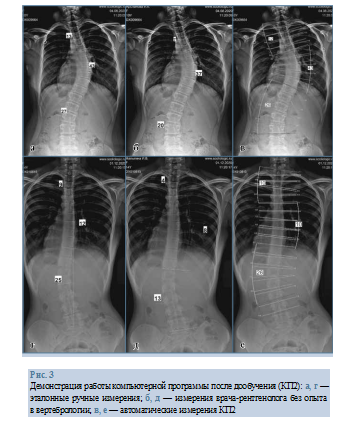

В заключение приведем пример работы КП2 по сравнению с эталонными измерениями и измерениями ВРБО (рис. 3).

Измерения ВРБО существенно отличались от эталона — от 4 до 12°. Программа правильно определила и оценила все имеющиеся дуги деформации, разница между эталонным и автоматическим измерением угла Cobb составила 1—2° и определена как несущественная.

Демонстрация работы компьютерной программы после дообучения (КП2): а, г — эталонные ручные измерения; б, д — измерения врача-рентгенолога без опыта в вертебрологии; в, е — автоматические измерения КП2